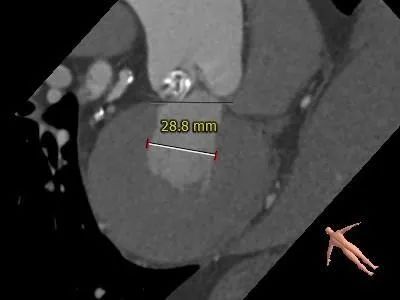

术前CT评估:

冠脉高度:

冠脉开口高度可,未见冗长瓣叶

冠脉开口高度可,未见冗长瓣叶,结合瓦氏窦、STJ内径综合预估,冠脉风险低

非横位心,主动脉弓宽度角度可,预估输送器可顺利过弓跨瓣